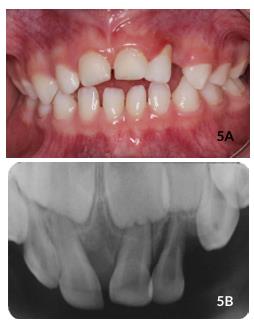

After 60 days, tooth #61 almost completely re-erupted and #62 completely re-erupted (Figures 4A and 4B), without color change,

Figures 3A y 3B Clinical and radiographic aspects after two weeks following trauma showing the beginning of the re-eruption process.

complaints of pain, inflammation or fistula. In addition, the gums looked healthy. Radiographically, there is no observed presence of periapical and periodontal lesions (Figure 4C). On the 8 months follow-up, it was found that tooth #61 re erupted satisfactorily, despite being slightly above the line of occlusion and the patient presenting an anterior open bite. Absence of gingival inflammation, fistula or pain was

Figures 4A,4B y 4C Clinical and radiographic aspects after 2 months following trauma with complete re- eruption of teeth.